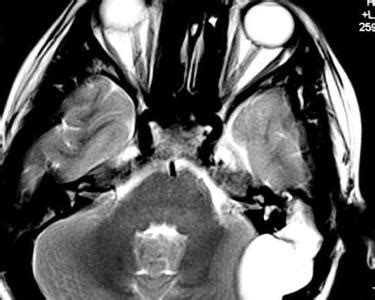

值得注意的是,良性肿瘤与恶性肿瘤之间有时并无绝对界限,有些肿瘤的表现可介于两者之间,称之为交界性肿瘤。例如膀胱的乳头状瘤具有良性细胞形态,但容易复发,甚至转变成恶性肿瘤。良性肿瘤如血管瘤多无包膜,界限不清,切除后容易复发。良性肿瘤发生在某些重要器官也可引起严重后果,例如颅内良性肿瘤(脑膜瘤、星形胶质细胞瘤)可压迫脑组织,阻塞脑室系统,导致极大的危害;又如发生在心脏的间皮瘤,仅数毫米大小,但可引起心律紊乱而导致患者猝死。恶性肿瘤也并非预后皆差,如皮肤基底细胞癌生长缓慢,几乎不发生转移,经治疗后能完全治愈。肿瘤的良恶性也并非一成不变,有些良性肿瘤如不及时治疗,可转变为恶性肿瘤,例如卵巢肿瘤可恶变为卵巢癌。偶尔,恶性肿瘤也可转变为良性肿瘤,例如儿童的一种恶性肿瘤神经母细胞瘤可转变为良性的节细胞神经瘤。